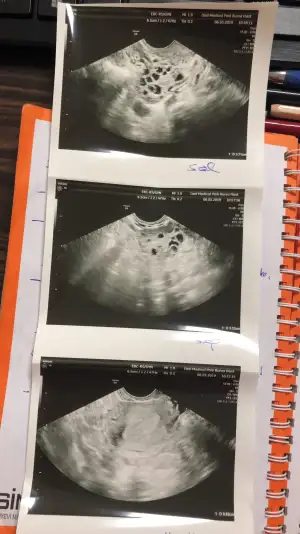

fsh ve lh değerlerin ne çıktıdoktor bugün hormon değerlerime baktı normal polikistik gibi gözükmüyor dedi kilo verince düzelebilir dedi ama böyle olan var mı merak ediyorum 22 yaşındayım bu yaşıma kadar hep normaldi sadece 3 aydır gecikmeler yaşıyorum son zamanlarda aşırı kilo aldım ona bağladım ben ama